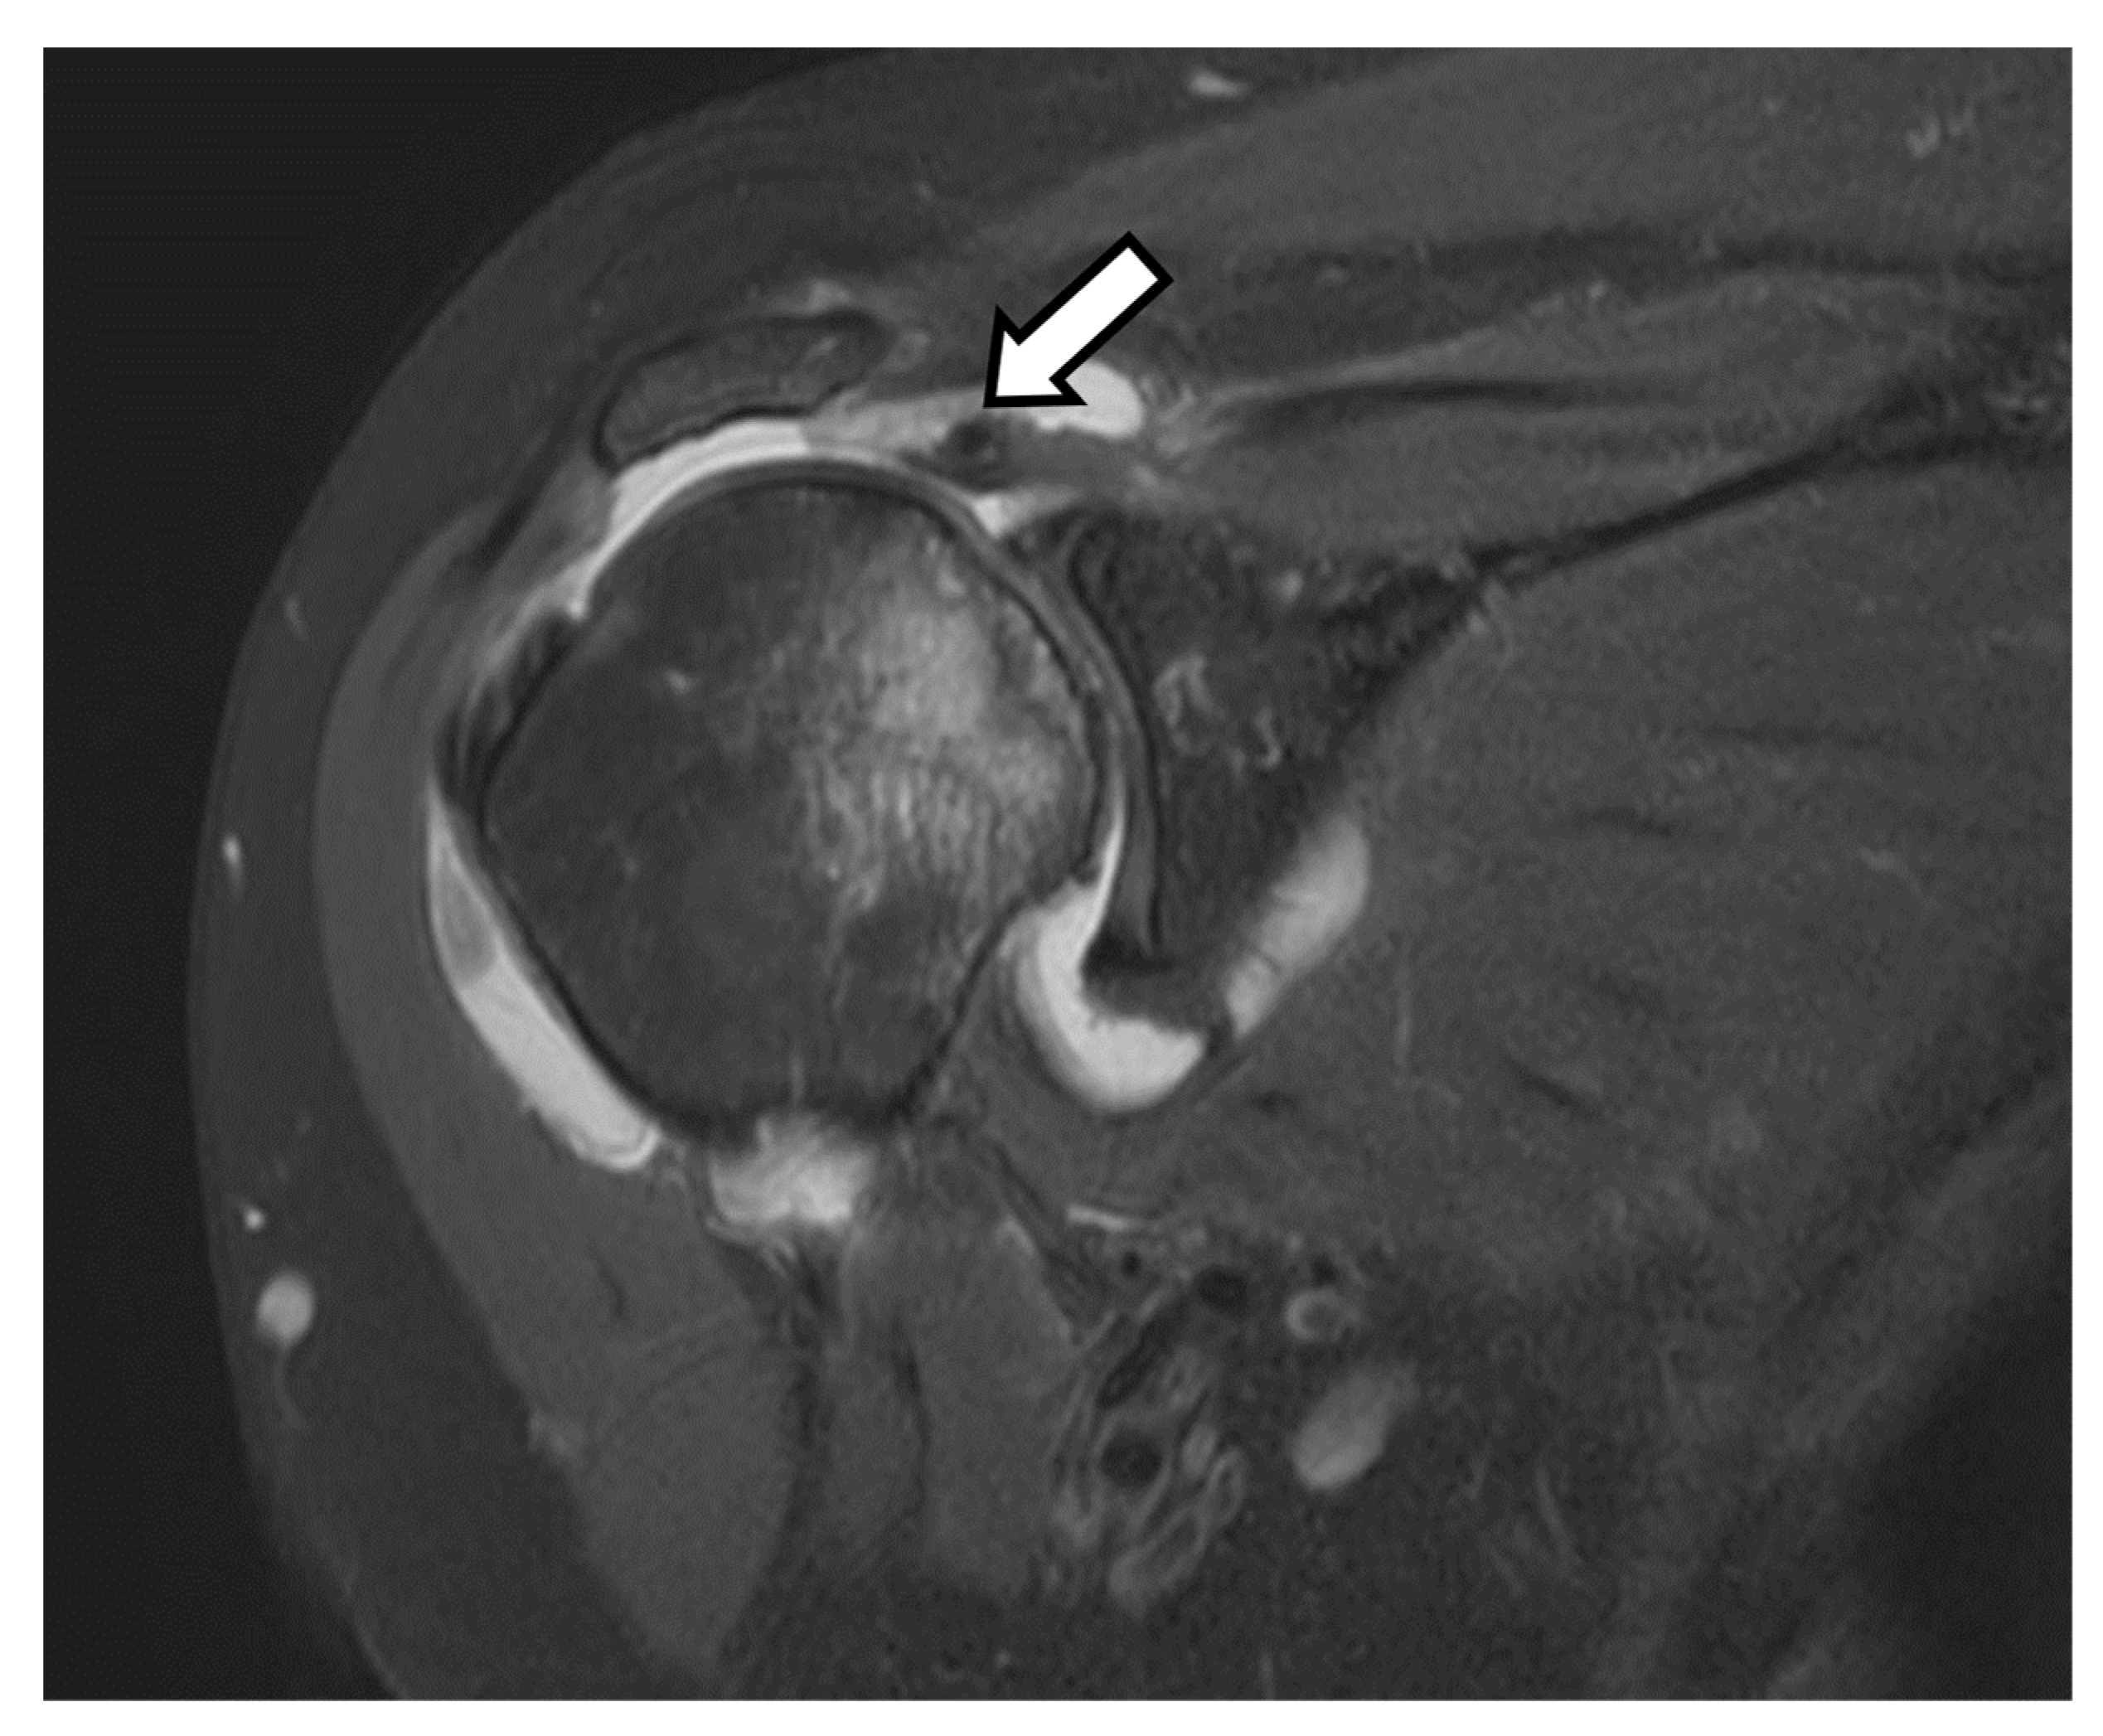

3. Preoperative Imaging

| Type | Description |

| A1 | Mild central glenoid erosion with the humeral head centrally positioned. |

| A2 | Major central glenoid erosion with the humeral head centrally positioned; a line that connects the native anterior and posterior glenoid rims transects the humeral head. |

| B1 | No glenoid erosion; posteriorly subluxed humeral head with posterior joint space narrowing and osteophytes. |

| B2 | Biconcave glenoid due to posterior erosion and retroversion, with posteriorly subluxed humeral head. |

| B3 | Monoconcave glenoid with significant posterior glenoid wear with retroversion of at least 15 degrees or subluxation of 70% or both. |

| C | Retroverted glenoid with glenoid dysplasia. |

| D | Anteverted glenoid or anteriorly subluxed humeral head. |